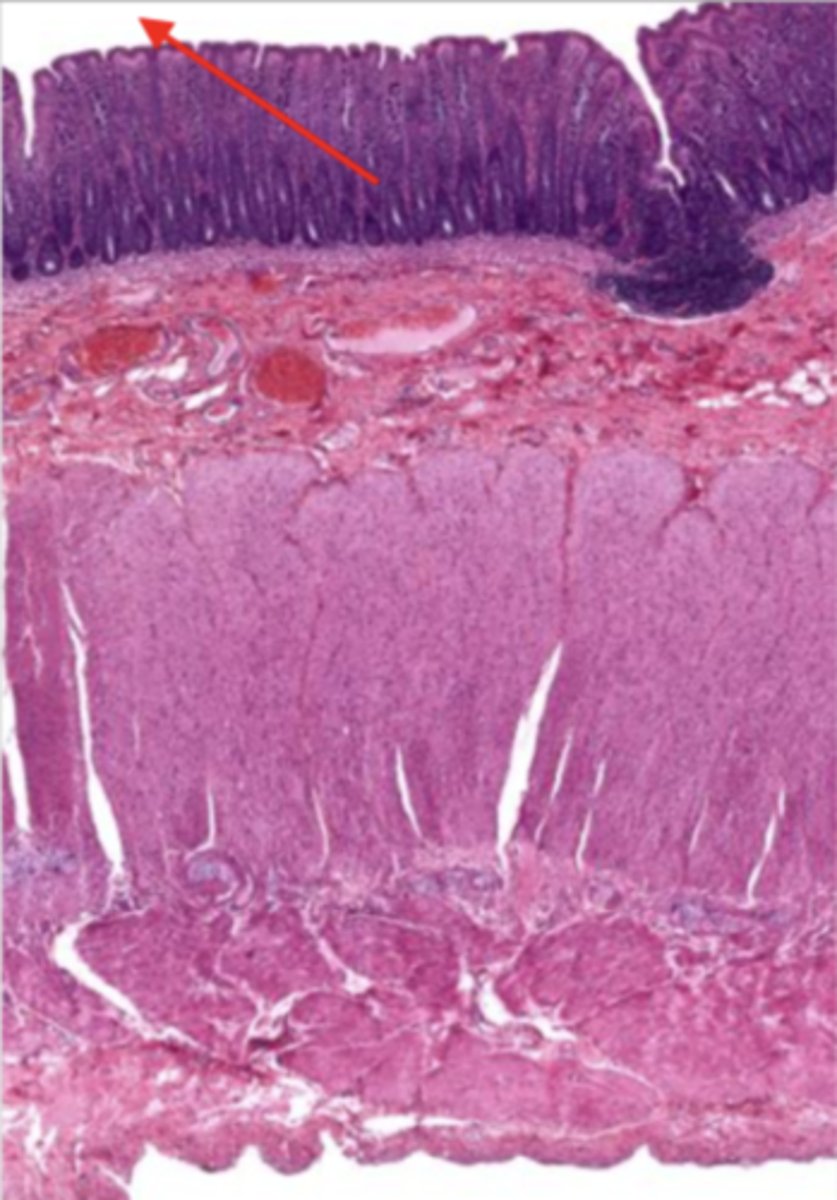

cardiac stomach (histology)

simple columnar epithelium

what kind of epithelium lines the mucosa of the cardiac stomach?

gastric pit (cardiac stomach)

lumen (cardiac stomach)

mucosa (cardiac stomach)

mucosal epithelium (cardiac stomach)

lamina propria (cardiac stomach)

muscularis mucosa (cardiac stomach)

submucosa (cardiac stomach)

contains glands and blood supply

muscularis externa (cardiac stomach)

serosa/adventitia (cardiac stomach)